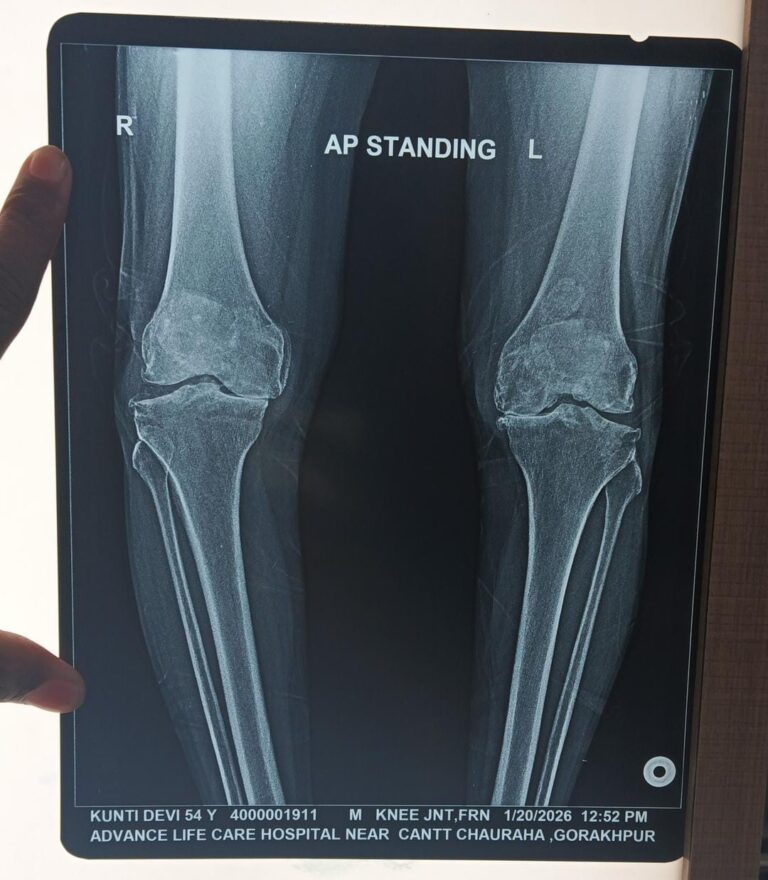

Mrs. Kunti Devi, aged 54 years, a resident of Alapur Barauli, Gopalganj, Bihar, had been suffering from severe knee pain for several years. Due to continuous pain and difficulty in walking, sitting, and performing daily activities, her quality of life was significantly affected.

During the consultation, the doctor carefully listened to her complaints and advised necessary investigations, including knee X-rays. The OPD slip was issued, and diagnostic tests were conducted on 09-02-2026. After reviewing the X-ray and detailed report, it was diagnosed that her knee joint was severely damaged due to advanced arthritis and degeneration.